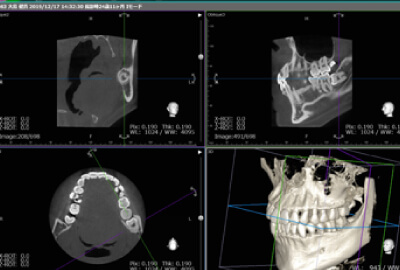

術前のカウンセリングで、抜歯の必要性を診査診断し、抜歯の必要がある場合、顎の神経に歯の根元が近くないかを確認し、安全に処置を進めていきます。歯の角度や根っこの形状をあらかじめ調べ、迅速かつ安全に抜歯します。当院では手術室をはじめ大学病院並みの設備を完備しており、抜歯における生体モニターやCT設備、検査機器を揃えています。滅菌された器具で清潔な環境を徹底しているので、安心して外科手術に臨んでいただくことができます。

埋もれている親知らずの歯の抜歯、口腔内の手術などを行う場合には、まずコンピューターでシミュレーションを行います。さらにCT画像︎を処理することで様々な角度から画像を分析し、より安全に治療を行うことが可能です。